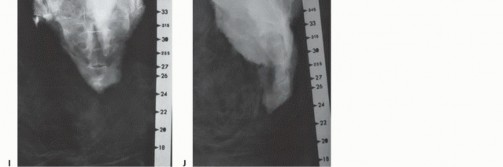

التصوير بالأشعة السينية العادية

قد تكون صور الأشعة السينية العادية غير واضحة في المراحل المبكرة من المرض. ومع ذلك، يمكن أن تساعد في تشخيص بعض الأورام، مثل الورم الحبلي الذي غالبًا ما يقع في الجزء السفلي من العجز، أو الأورام الكبيرة والمحللة تمامًا مثل ورم الخلايا العملاقة أو الكيس العظمي المتمدد في الجزء العلوي من العجز. تُعد الأشعة السينية ضرورية لإعطاء نظرة عامة ومتابعة ما بعد الجراحة.

التصوير المقطعي المحوسب والرنين المغناطيسي

- التصوير المقطعي المحوسب (CT): يُعد بتقنية التباين الوريدي الأسلوب الأمثل لتقييم مدى انتشار الورم في العظم وتدميره، والتكلسات المحتملة، والموقع التشريحي، والإمداد الدموي، وعلاقة الورم بالأعضاء الحشوية. يساعد في التفريق بين الأورام الحميدة والخبيثة.

- التصوير بالرنين المغناطيسي (MRI): بتقنية التباين، يُعد حاسمًا لتصوير الأنسجة الرخوة ومدى انتشار الورم فيها، وعلاقته بالأنسجة المحيطة (مثل الأوعية الدموية والأعصاب والعضلات والأعضاء الحشوية). يُعتبر الأسلوب الأمثل لتصوير الأنسجة الرخوة نظرًا لقدرته الفائقة على التمييز مقارنةً بالتصوير المقطعي.